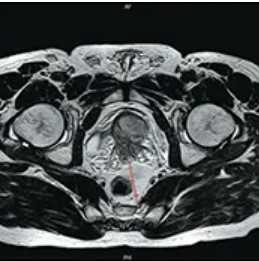

Пациент К., 1965 года рождения, при плановом обследовании в поликлинике по месту жительства в марте 2017 г. выявлено повышение уровня ПСА до 6,5 нг/мл, в связи с чем в ГКБ № 29 Москвы выполнена трансректальная биопсия предстательной железы, гистологически верифицирована ацинарная аденокарцинома 6 (3+3) баллов по Глисону. Больной самостоятельно обратился в МНИОИ им. П.А. Герцена. При пересмотре стекол препаратов биопсии предстательной железы в условиях патоморфологического отделения МНИОИ им. П.А. Герцена на фоне гиперплазии предстательной железы с очагами атрофии в 5 фрагментах из 12 выявлен рост ацинарной аденокарциномы 7 (4+3) баллов по Глисону, занимающей до 100% площади столбиков. По данным УЗИ и МРТ малого таза, предстательная железа размером 42×34×30 мм, объемом до 30 см 3 (рис. 3). Рис. 3. Магнитно-резонансная томограмма малого таза.

В периферической зоне правой доли определяется очаг раннего накопления контрастного препарата 13×10 мм без инвазии в капсулу железы и семенные пузырьки. В полости малого таза измененные лимфатические узлы не выявлены. При пальцевом ректальном исследовании предстательная железа не увеличена в размере, не деформирована, эластической консистенции, без пальпируемых узловых образований, междолевая бороздка сглажена. Слизистая оболочка прямой кишки над железой подвижна. Другой очаговой опухолевой патологии при комплексном обследовании не выявлено. На основании обследования установлен клинический диагноз: рак предстательной железы I стадии сТ2аN0M0. Больной обсужден на консилиуме с участием хирурга, химиотерапевта, лучевого терапевта и онколога: учитывая размер, локализацию и распространенность опухолевого процесса, отсутствие отдаленных и регионарных метастазов, рекомендовано хирургическое лечение. 10.04.17 больному выполнено хирургическое лечение в объеме радикальной простатэктомии, расширенной тазовой лимаденэктомии. Послеоперационный период протекал гладко, без особенностей. При контрольном УЗИ органов малого таза и вен нижних конечностей от 17.04.17 в полости малого таза объемных образований не выявлено. Поверхностные и глубокие вены обеих конечностей проходимы, без тромбоза и флебита. По данным цистографии от 17.04.17, подтверждена герметичность везикоуретрального анастомоза, в связи с чем 19.04.17 уретральный катетер удален, восстановлено самостоятельное мочеиспускание. Проведены антибактериальная, инфузионная, симптоматическая терапия и профилактика тромбоэмболических осложнений с положительным эффектом. Послеоперационная рана зажила первичным натяжением.